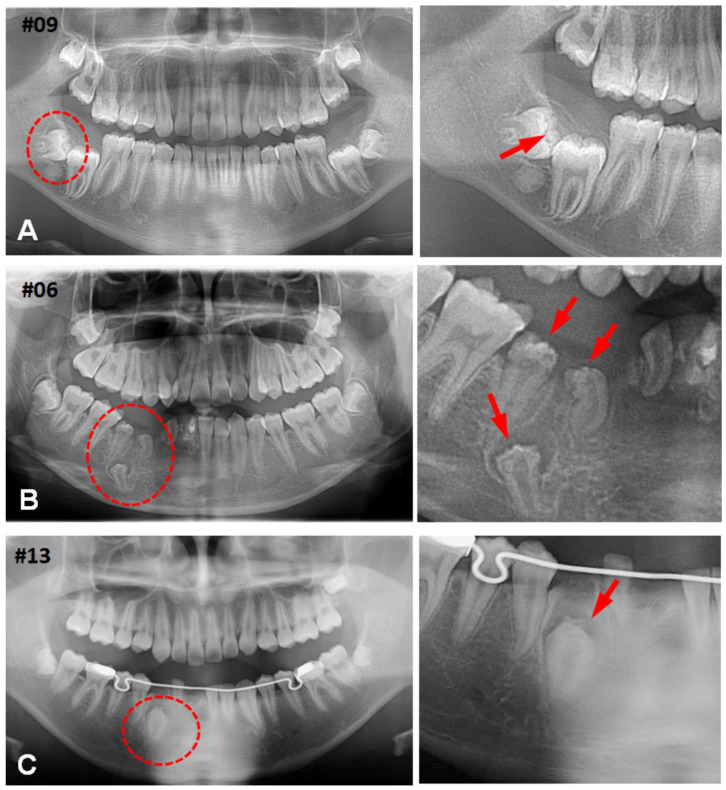

Hyperplastic dental follicles (HDFs) represent odontogenic hamartomatous lesions originating from the pericoronal tissues and are often associated with impacted or embedded teeth. These lesions may occasionally feature unique calcifying bodies, known as calcifying whorled nodules (CWNs), characterized by stromal cells arranged in a whorled or spiral fashion. CWNs are typically observed in multiple calcifying hyperplastic dental follicles or regional odontodysplasia. In our study, we examined 40 cases of HDFs, including nine instances with characteristics of CWNs, referred to as calcifying hyperplastic dental follicles (CHDFs), which are infrequently accompanied by odontodysplasia. The median ages of the HDFs and CHDFs were 16 (ranging from 3 to 66) and 15 (ranging from 11 to 50) years, respectively. The lower third molars were the most frequently affected by HDSFs and CHDFs, followed by the upper canines. A histological examination was conducted on all 40 cases, with an immunohistochemical analysis performed on 21 of them. Among the cases with CWN, nine affected a single embedded tooth, with one exception. CWNs exhibited diverse calcifications featuring sparse or entirely deposited psammoma bodies, and some displayed dentinoid formation. Immunohistochemically, the stromal cells of HDFs were frequently positive for CD56 and nestin. By contrast, CWNs were negative for CD56 but positive for nestin as well as hairy and enhancer split 1 (HES1), with a few dentin sialoprotein (DSP)-positive calcified bodies. Our results revealed that hamartomatous CHDFs can impact multiple and single-embedded teeth. CWNs composed of nestin and HES1-positive ectomesenchymal cells demonstrated the potential to differentiate into odontoblasts and contribute to dentin matrix formation under the influence of HES1. This study is the first report documenting odontoblastic differentiation in HDFs. The rare occurrence of HDFs and CHDFs contributes to limited comprehension. To prevent misdiagnosis, a better understanding of these conditions is necessary.